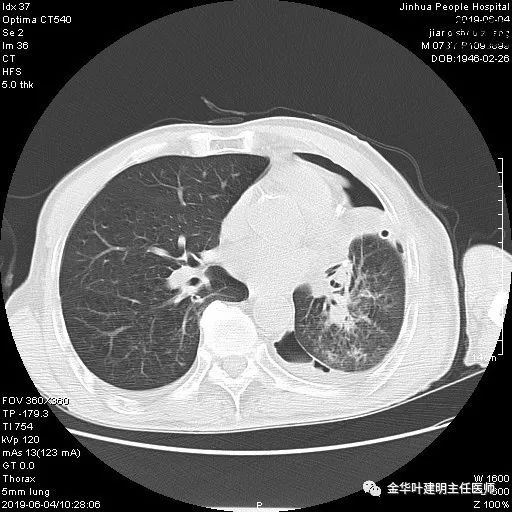

6.4上午:24小时引流出血性乳糜液1800毫升。是否再次手术进行右进胸胸导管结扎,抑或继续保守治疗非常纠结!压力非常大!!多方讨论会诊无法取得一致意见,但一般认为,引流量在1000毫升以上宜积极手术。情况与浙二医院范军强教授联系,请求指导,范教授认为左侧肺手术,损伤胸导管主干的机会较小,多数可保守治疗而愈。在他们的病例中,也有结扎胸导管后引流量仍无减少,效果并不能完全保证。建议可以考虑胸管夹管观察(因为淋巴管压力低,予以适当的压力,漏出量可能会明显减少),同时继续禁食,并静脉营养支持,引流管口可能会有渗液,注意更换敷料。与家属充分沟通后决定试夹管;这天血色素9.0 g/L;胸部CT复查示: